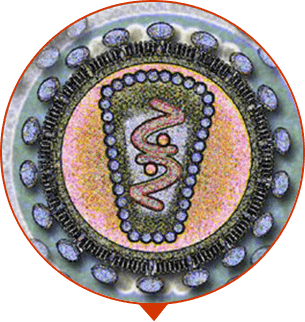

Hochentwickelte Technologien und 100% ökologisch verträgliche Komponenten ohne Chemie

Die Zusammensetzung von Prostalium+ spricht für sich. Das ist ein absolut sicheres Mittel für die Männer der älteren Generation. Dank einzigartiger Formel und Konzentration der aktiven Komponenten, der Vitamine entfernt die Entzündung, regeneriert die Erektion, Prostatitis kehrt nicht zurück. Der Männerkörper arbeitet wie schweizerische Uhr.

WIRKSAME WIRKUNG OHNE NEBENEFFEKTE

Hochentwickelte Technologien ermöglichen es das kristallklare reine beimischungsfreie Konzentrat der heilsamen Pflanzen zu bekommen